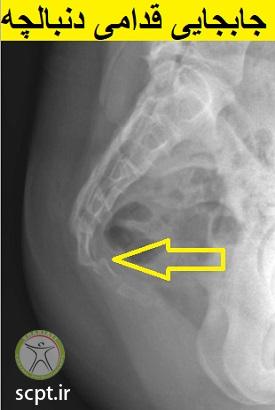

در مواردی که علت ایجاد درد دنبالچه ضربه می باشد ممکن است که این ضربه منجر به درد مزمن در ناحیه دنبالچه شود. ضربات وارده به دنبالچه به دو دسته ضربات بدون جابجایی دنبالچه و ضربات با جابجایی دنبالچه تقسیم بندی می شوند.

ضرباتی که میتوانند سبب جابجایی استخوان دنبالچه و استخوان ساکروم شوند میتوانند منجر به درد در ناحیه دنبالچه و اطراف آن شوند عمده دردها که منجر به شکستگی نمیشوند مرتبط با دردهای لیگامان ها ( رباط ) ی متصل کننده دنبالچه و ساکروم می باشند که در شکل های زیر ملاحظه می نمایید.